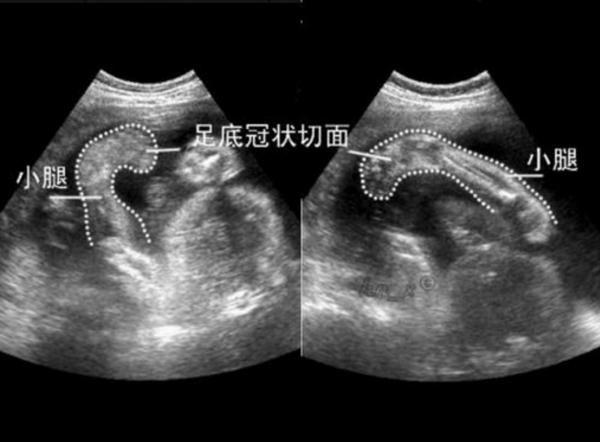

产前超声提示:胎儿双足内翻——别怕,好解决

再谈胎儿足内翻超声诊断与处理